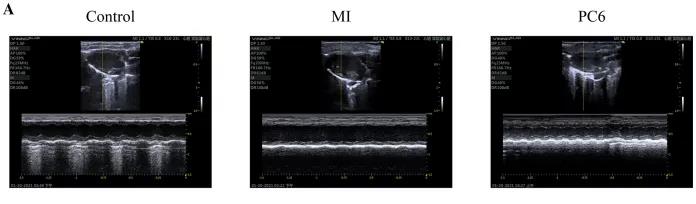

成年雄性C57BL/6雄性小鼠隨機(jī)分為對(duì)照組、MI組和PC6組。MI組小鼠為通過結(jié)扎冠狀動(dòng)脈左前降支(LAD)形成MI模型,PC6組在造模完成后,針刺內(nèi)關(guān)穴治療5天后取材。經(jīng)胸超聲心動(dòng)圖評(píng)估MI手術(shù)前后小鼠心功能情況,并進(jìn)行血清心肌酶和炎癥細(xì)胞因子的測定,之后三組樣本各取3個(gè)重復(fù),共9個(gè)樣本進(jìn)行ONT全長轉(zhuǎn)錄組測序。

為了探討針刺PC6穴對(duì)心肌損傷的影響,作者首先評(píng)估了心功能和梗死面積。超聲心動(dòng)圖結(jié)果顯示MI組的EF(ejection fraction)和FS(fractional shortening)均較對(duì)照組明顯降低。PC6穴位治療后,EF和FS均增加。針刺治療5天后, 采用TTC染色檢測梗死面積。結(jié)果顯示,針刺治療顯著減小心肌損傷的大小。采用ELISA法測定反映急性心肌損傷的心肌特異性血清酶,包括心肌肌鈣蛋白T (cTnT)和心肌肌鈣蛋白I (cTnI)的水平。結(jié)果表明,心肌梗死術(shù)后cTnT和cTnI水平升高,針刺可顯著降低血清酶水平。